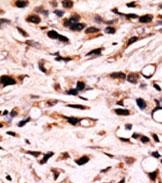

- Formalin-fixed and paraffin-embedded Breast Carcinoma reacted with SMAD4-T277 (center) (Cat.#P30236), which was peroxidase-conjugated to the secondary antibody, followed by DAB staining. This data demonstrates the use of this antibody for immunohistochemistry; clinical relevance has not been evaluated.